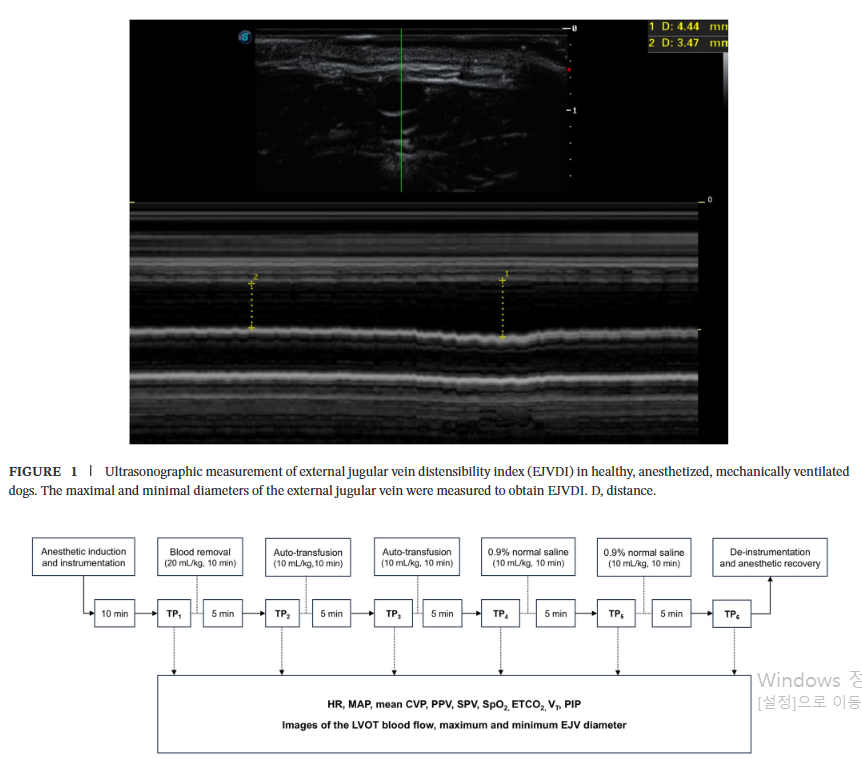

측정 방법해당 부위에서 초음파 탐촉자(probe)를 피부에 수직으로 위치시켜 외경정맥의 횡단면(transverse plane)을 B-모드(B-mode)로 확인했습니다. 이후 M-모드(M-mode)를 이용하여 호흡 주기에 따른 직경의 변화를 기록하였습니다. 이때 정맥이 눌리지 않도록 최소한의 압력만 가하여 측정했습니다. |

각 단계에서 연구진은 심박수, 혈압, 중심정맥압(CVP) 등 기본적인 혈역학 지표와 함께, 초음파를 이용하여 좌심실 유출로 혈류 속도(LVOT VTI)와 외경정맥(EJV)의 직경을 측정했습니다. 외경정맥의 직경은 호흡 주기에 따라 가장 커졌을 때(흡기, )와 가장 작아졌을 때(호기, )를 각각 측정하여 다음 공식으로 EJVDI를 계산했습니다.